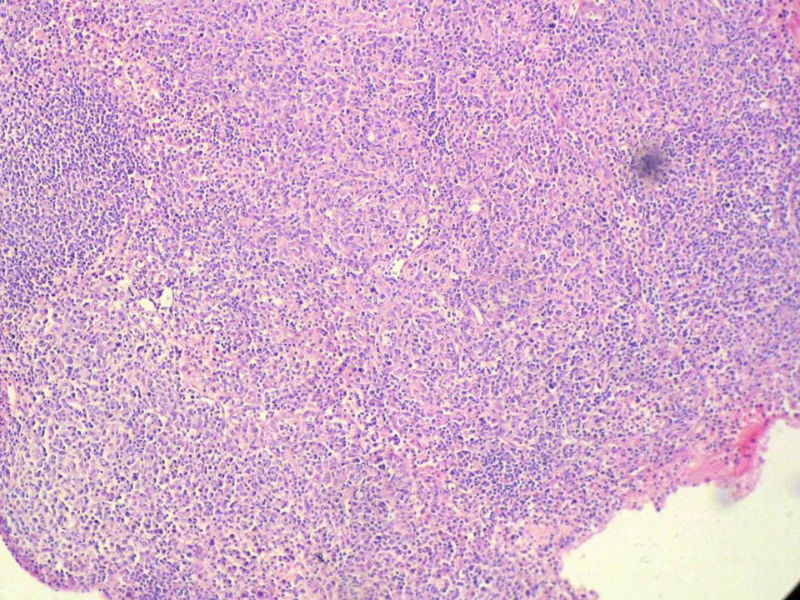

Ki-67标记在淋巴滤泡(生发中心)细胞全阳性,而且显示出生发中心边缘规则,不像是肿瘤,呈反应性增生。

Ki-67标记在滤泡间和淋巴组织弥漫增生区见散在阳性细胞,这些阳性细胞可能是转化性淋巴细胞,有的甚至是内皮细胞或组织细胞。

请看下图,显示的细胞比较杂,胞浆较丰富,胞核没有什么特别的异型性。没有促纤维增生反应和围血管生长表现,没有肿瘤性坏死,没有见到更多的核分裂,特别是病理性核分裂。因此认为,本例是淋巴组织反应性增生,可能是对病毒感染的反应。